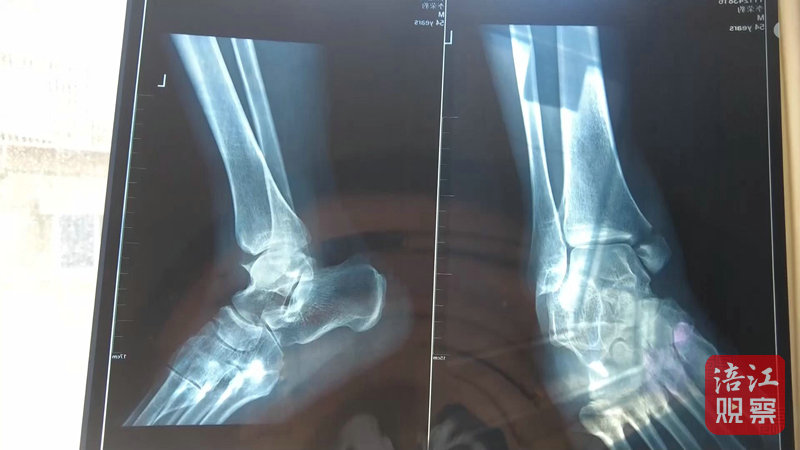

4月22日,記者來(lái)到綿陽(yáng)市骨科醫(yī)院,病房?jī)?nèi),李先生正在進(jìn)行術(shù)后上下床的康復(fù)訓(xùn)練。李先生的主治醫(yī)生介紹,李先生因左內(nèi)踝骨折入院,手術(shù)一周后傷口愈合良好,病情穩(wěn)定,目前已轉(zhuǎn)入康復(fù)科進(jìn)行康復(fù)功能鍛煉。